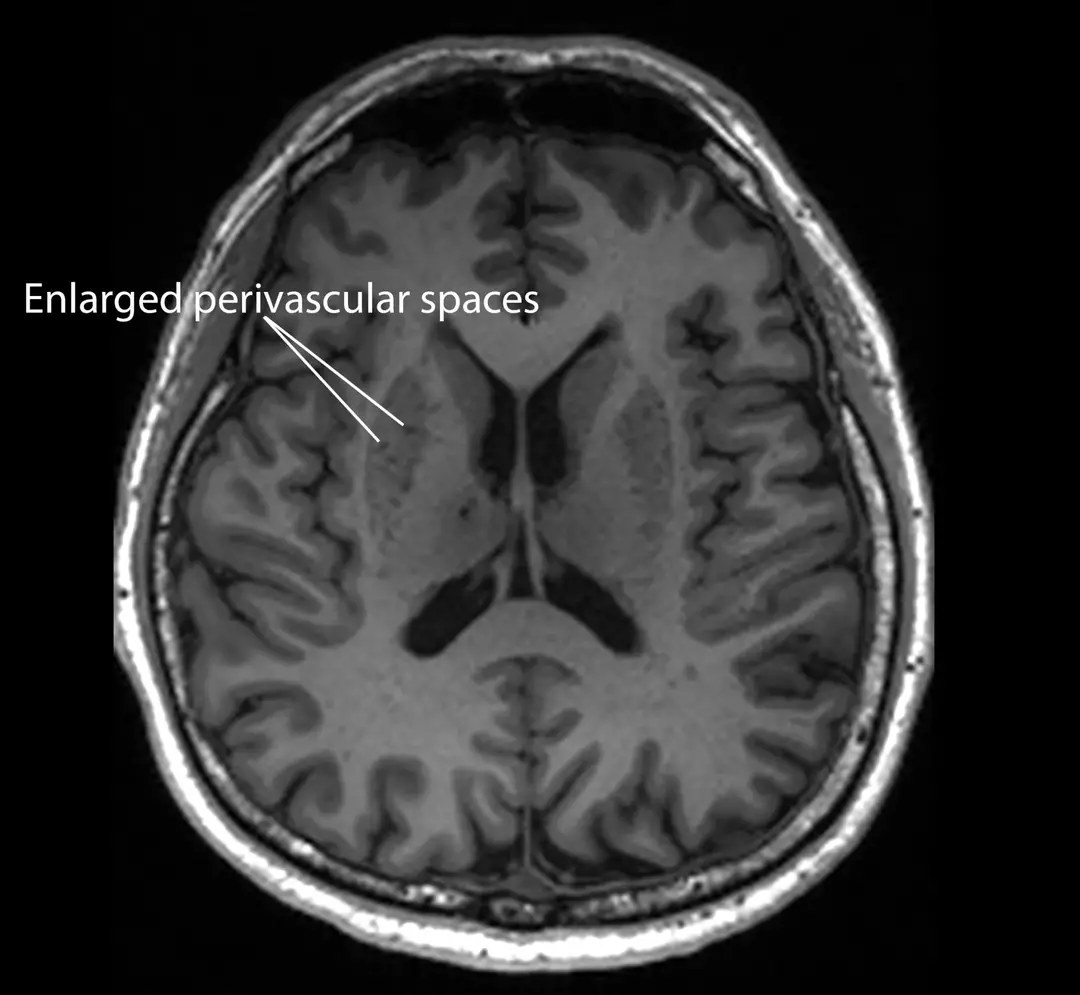

They found that clogged drainage spaces in the brain, which can be seen on scans, are associated with early indicators of dementia.

These drainage spaces are responsible for removing toxic waste from the brain but can become enlarged when obstructed.

Referred to as enlarged perivascular spaces, they are detectable on standard Magnetic Resonance Imaging (MRI) scans.

These enlarged spaces have been linked to other Alzheimer’s indicators, including increased amyloid plaques, more tau tangles, and signs of brain cell damage.

This observation suggests that the clogging occurs before significant brain damage, making it a promising marker for early detection.

“Since these brain anomalies can be visually identified on routine magnetic resonance imaging (MRI) scans performed to evaluate cognitive decline, identifying them could complement existing methods to detect Alzheimer’s earlier, without having to do and pay for additional tests,” explained Associate Professor Nagaendran Kandiah, who led the study.